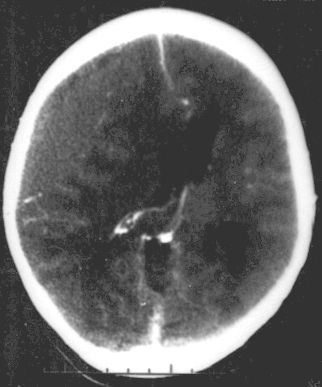

El herido ingresó al Hospital Perrupato y luego fue derivado de urgencia al Hospital Central, donde está internado. Ya lo operaron por dos grandes problemas físicos que tiene tras el impacto. El primero es una acumulación de sangre en la cabeza a causa del golpe, lo que resulta riesgoso porque sube notablemente la presión intracraneal, pudiendo derivar en la muerte. El otro inconveniente por el que debieron intervenir los cirujanos fue un hemotórax: una acumulación de sangre en el espacio existente entre la pared torácica y el pulmón.